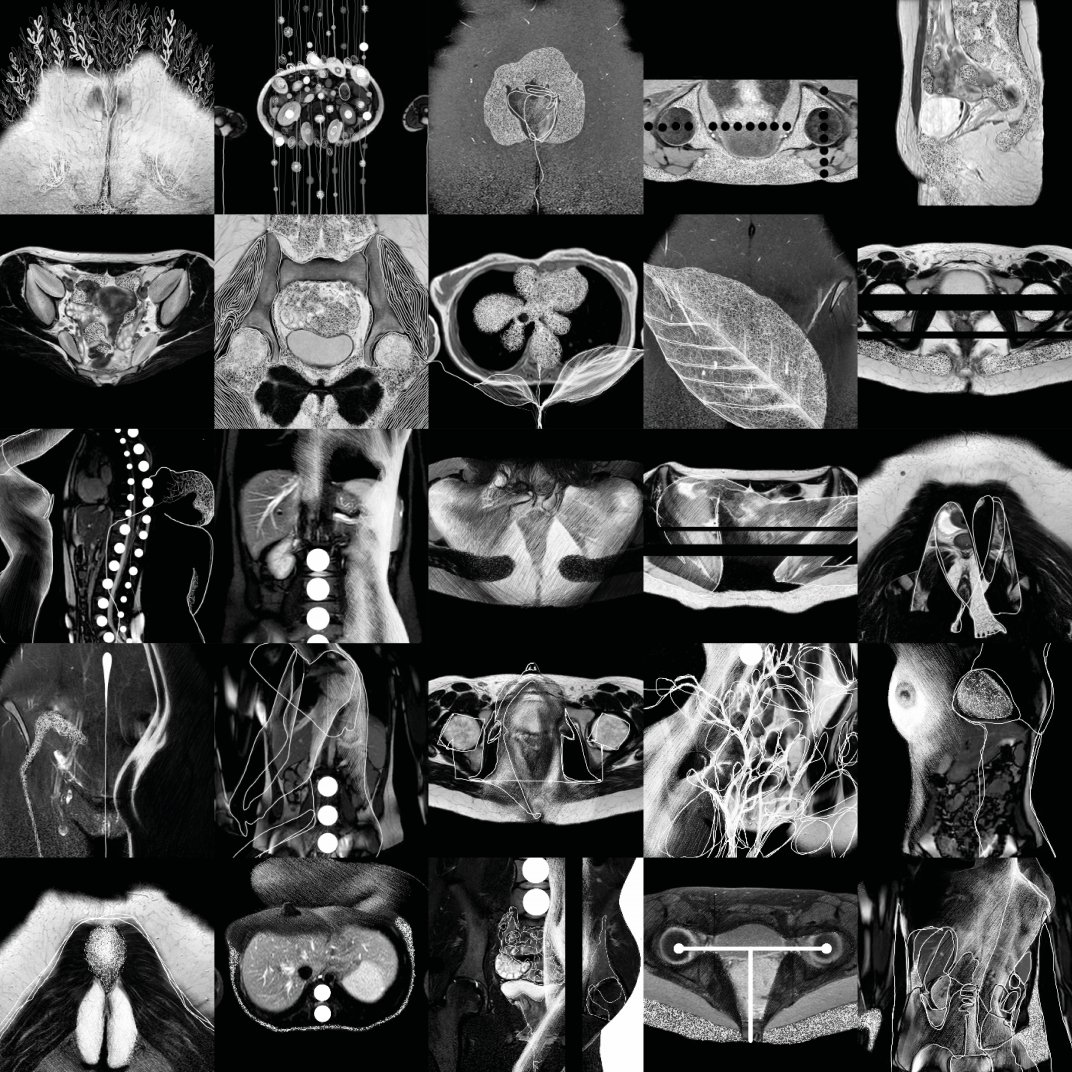

Printing on aluminum 100x100, imagines of abdominal MRI scan and digital drawing, 2019.

The images were arranged in series and assembled together, to refer conceptually to a tabular order classifying diseases, which reduces the bodies of sick people into alpha-numerical codes, depriving them of identity. The arrangement is not random but numbered and should be read as a progressive and growing introspection. The choice to assemble the sequences in a single image shows on one hand the desire to standardize the depersonalizing photographic fragmentation of each single portion of the body created by MRI and on the other hand to bring the body back to art as a unicum, concentrating the gaze of the viewer on the entire content of the work.